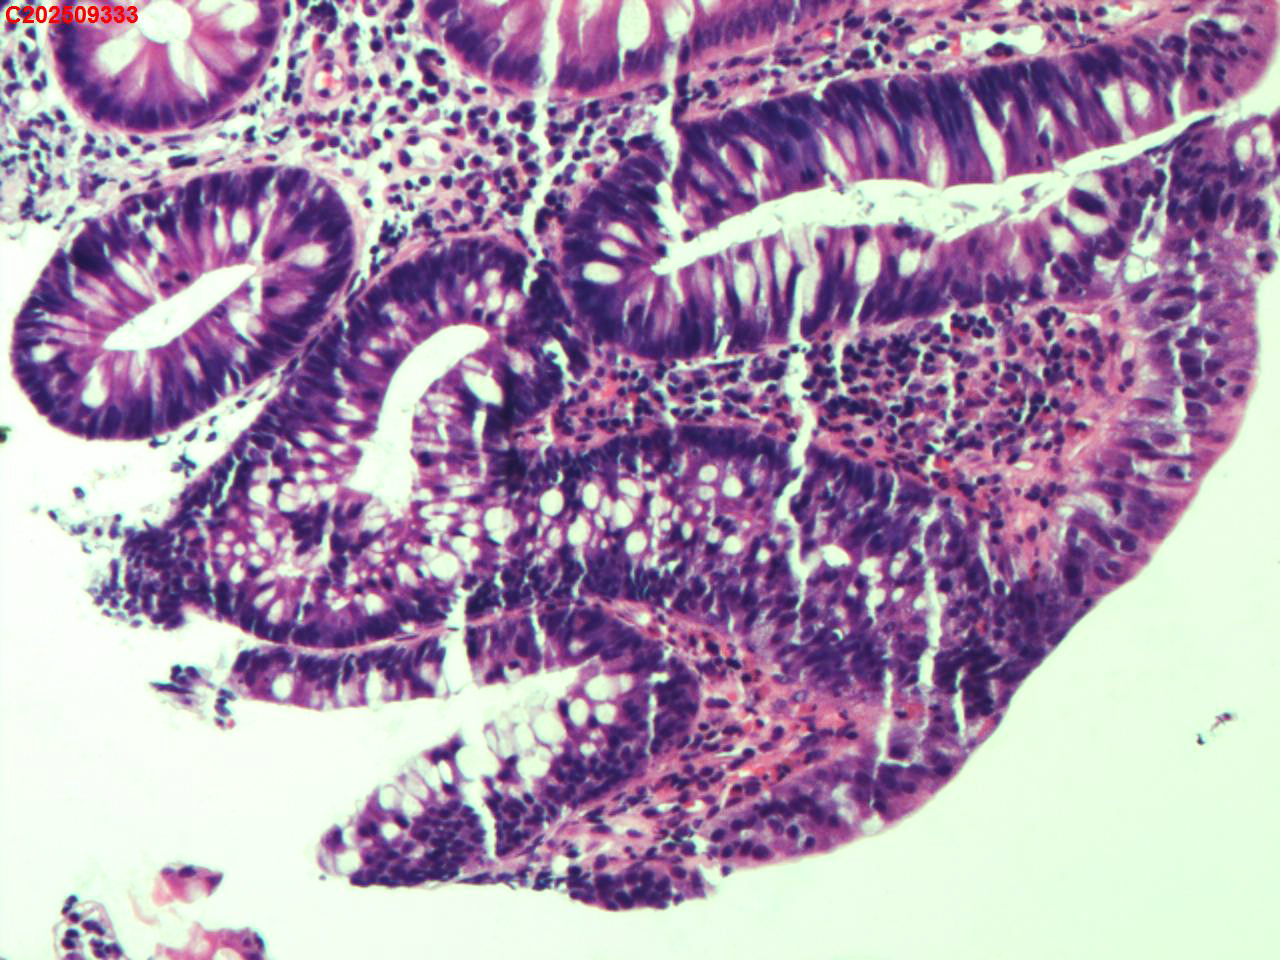

回盲部粘膜

性别

男

年龄

66岁

临床诊断

结肠息肉

一般病史

体检

标本名称

大体所见

回盲部可见直径约4mm息肉样隆起。

小灶腺上皮低级别异型增生(考虑是一个比较早期的管状腺瘤)。